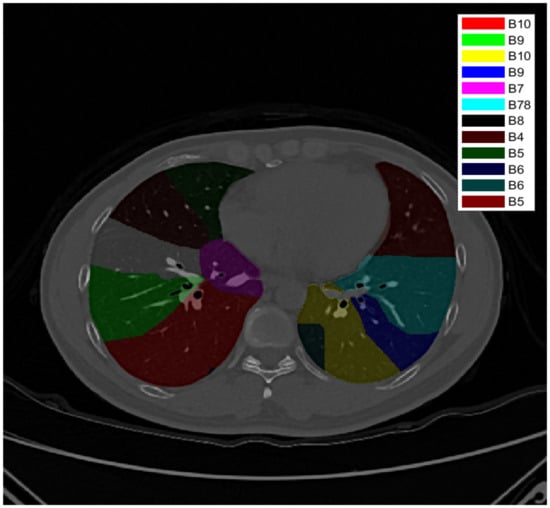

3.3. Pulmonary Airway Circling

Due to the restrictions of CT and the effects of diseases and noise, the pulmonary airway wall is sometimes fractured or injured. It should be repaired before the pulmonary airway is circled. Each pixel of the lung mask is given a score to assess how much the pixel looks like an airway (blood vessel). The pixel of a probably ruptured airway wall is judged according to the plane’s position distribution of pixel scores, as shown in Figure 5.

Figure 5.

Pulmonary airway wall repair. Here, (a) is the original image, (b) is the score given according to three-stage segmentation; blue (air) is 0 point, red (uncertain) is 1 point, and green (airway wall and blood vessel structures) is 2 points, and (c) is the result of repair after the mask weight score is applied.

The uncertain pixels are dualized to air or not air to generate a mask. The pixel values in the original image are changed to a K-means tissue part and other object cluster centers of high radiation shielding according to the mask to complete filling.

After filling, the closed dark pixels are detected by the grayscale reconstruction method, as shown in Figure 6. Grayscale reconstruction masks of different detection radii are connected using a six-adjacency relation to complete pulmonary airway detection. Figure 7 shows the 3D visualization result of the circled airways.

Figure 6.

Grayscale reconstruction flow chart. (a) Original image; (b) labeled image; (c) grayscale reconstruction image; (d) local difference image; (e) local valley target; (f) original image marked with local valley target.